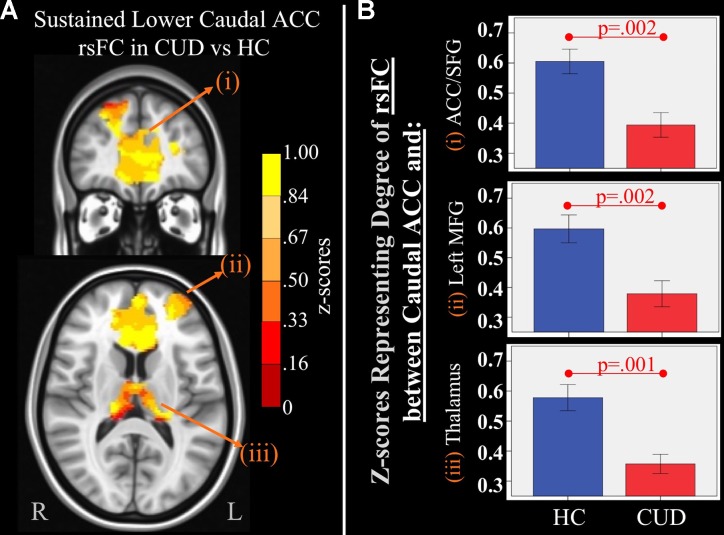

Sustained Group rsFC Differences

There were several significant main effects of group. CUD showed sustained lower rsFC (vs. HC) between the caudal ACC seed and: a) a cluster comprised of the right superior frontal gyrus, dorsal and rostral ACC (f3), b) left middle frontal gyrus (f3), and c) bilateral medial dorsal and anterior thalamic nuclei (f3). CUD also showed sustained lower rsFC (vs. HC) between the dorsal ACC seed and bilateral middle frontal gyrus (f4). All but one effect (the group difference in dorsal ACC rsFC with the left middle frontal gyrus) remained significant when nicotine use and IQ, together with alcohol use, were also covaried in a post hoc analysis. Additionally, ANCOVA results (“Methods,” section Data Denoising) showed that after controlling for the effects of the sum of percent of variance accounted for by noise, differences in all clusters, shown in f3 and f4, were still significant (see F– and P-values in T5).

Table 5: Significant main effect of group. Montreal Neurological Institute (MNI) coordinates of clusters (center of mass) in which resting functional connectivity (rsFC) of regions of interest (ROIs) showed a significant (per-voxel p = .001, cluster p = 0.025) main effect of group (non-treatment-seeking individuals with cannabis use disorder vs. healthy controls). No significant main effects of group were found for other regions of interest. F and significance (Sig) p-values show ANCOVA results controlling for the effects of differences in the sum of percent of variance accounted for by noise.

| ROI | rsFC with: | Hemis-phere | Brod-mann area | x, y, z | F | Sig (p-value) | Cluster size (# voxels) |

|---|---|---|---|---|---|---|---|

| Caudal anterior cingulate cortex (ACC) | Medial dorsal nucleus of the thalamus | Bilateral | — | 1, −18, 5 | 16.27 | .00023 | 1,940 |

| Dorsal and rostral ACC and superior frontal gyrus (SFG) | Bilateral ACC, left SFG | 9, 10, 32 | −1, 39, 16 | 14.40 | .00048 | 6,877 | |

| Medial frontal gyrus | Left | 10 | −30, 54, 16 | 14.13 | .00053 | 684 | |

| Dorsal ACC | Medial frontal gyrus and superior frontal gyrus | LeftRight | 1010 | −29, 59, 1126, 61, 14 | 14.1711.57 | .00052.00151 | 293276 |

Sustained Group rsFC Differences

While another study has reported immediate detrimental effects of cannabis manifested as reductions in rsFC within the default mode network (ref. 52), the current study provides additional supportive evidence of persistent frontal rsFC disruptions (caudal and dorsal ACC) in young adults with CUD. These disruptions could reflect pre-existing liabilities, or it may be that neurotoxic effects of cannabis asymptote persist into young adulthood. Our previous longitudinal fMRI study in adolescents reported that at baseline, rsFC of frontal networks was similar between adolescents with CUD and healthy controls. However, at follow-up, rsFC in individuals with CUD had significantly dropped when compared to HCs (ref. 19), supporting the idea that chronic CUD exerts protracted neurotoxic influences on the intrinsic functional organization of networks that mediate executive control, consistent with previous task-based fMRI studies (ref. 53). Since rsFC represents the functional architecture of brain networks (ref. 54), the quality of rsFC is a measurable manifestation of ongoing state-based brain functional organization that may underlie behavioral alterations (ref. 55, ref. 56). Persistent rsFC alterations of motor and cognitive control networks found in CUD may render them vulnerable to motor disinhibition (i.e., caudal ACC) (ref. 57), poor conflict monitoring, poor decision making, and poor learning (i.e., dorsal ACC) (ref. 29, ref. 58) on a daily basis, which may facilitate further substance misuse.